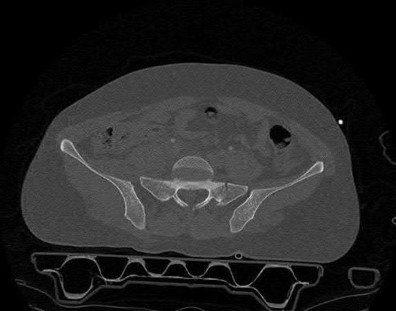

A 35 year-old female presents after prolonged extrication from a motor vehicle collision complaining of severe pelvic pain. Physical examination reveals diminished perianal sensation. She is otherwise neurologically intact. Figures A through D are radiographs and representative CT cuts of her injury. Which of the following nerve roots has likely been injured by the acute trauma?

The clinical scenario is consistent with a high-energy sacral fracture. The radiographs in figures A and B demonstrate a sacral fracture with posterior displacement of the right hemipelvis seen on the inlet view. Figures C and D are axial and sagittal CT images which show a displaced fracture of the right

hemisacrum along with a transvere fracture component through the S3 body . Diminished perianal sensation is concerning for an S2 nerve root injury.

Mehta et al reviewed the current management of sacral fractures. They note that the S1 and S2 nerve roots are more likely to be injured with sacral fractures as they occupy 1/3 to 1/4 of the neural foramina, as opposed to S3 and S4, which only occupy 1/6 of the neural foramina.

Robles reviewed the current literature to ascertain principles of evaluation and treatment for transverse sacral fractures. The author notes that injury to nerve roots S2 to S5 is manifested by impairment of urinary and anal continence and sexual function.